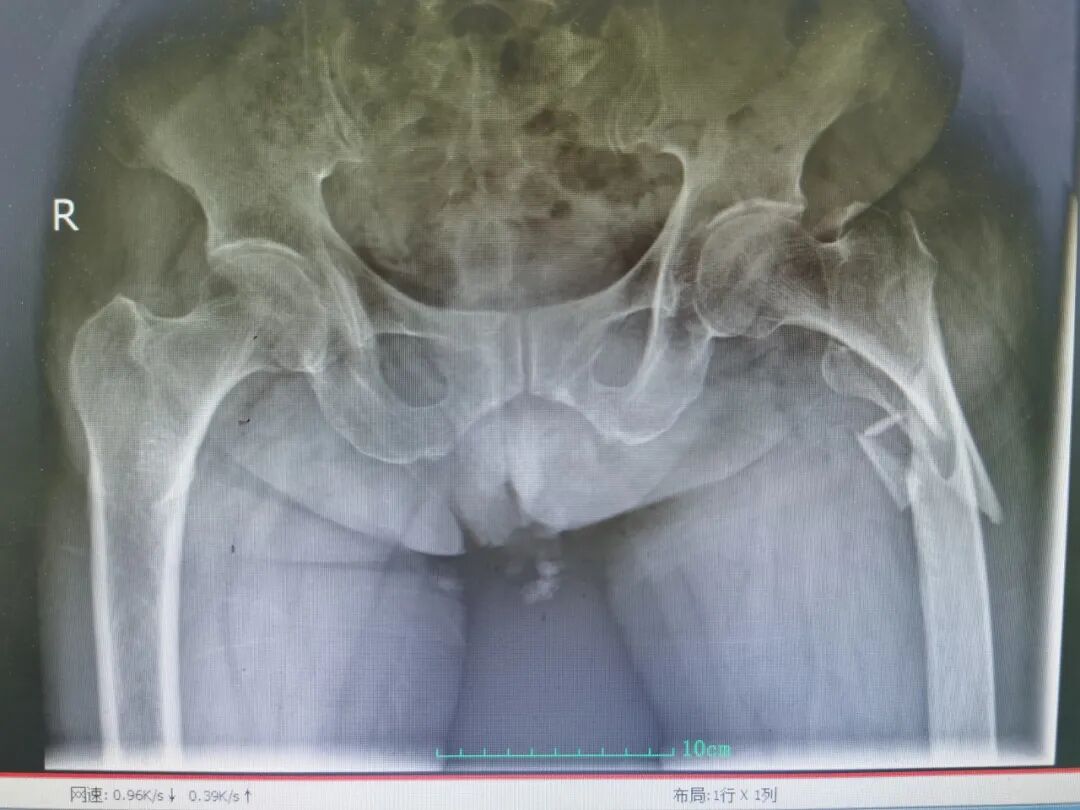

90岁的慕奶奶(化名)在家中不慎摔倒,当即出现左髋部剧痛、无法活动的情况,被紧急送至青岛西海岸第二医院就诊,经检查确诊为左侧股骨粗隆下粉碎性骨折,这正是让老年患者闻之色变的 “人生最后一次骨折”。

(术前影像)

而骨折只是冰山一角,慕奶奶(化名)的身体还藏着多重致命隐患:重度骨质疏松、高血压、心肌梗死支架术后、慢性心力衰竭,还伴有失血性贫血(术前血红蛋白仅 90g/L)、肥胖合并严重低蛋白血症(白蛋白仅 30g/L),术前超声发现其存在双侧下肢深静脉血栓,血栓随时可能脱落引发致死性肺栓塞,低蛋白血症让伤口愈合能力极差、感染风险飙升,心衰则让输血、输液都面临着循环超负荷的致命风险,11 项诊断让整个救治工作如履薄冰。